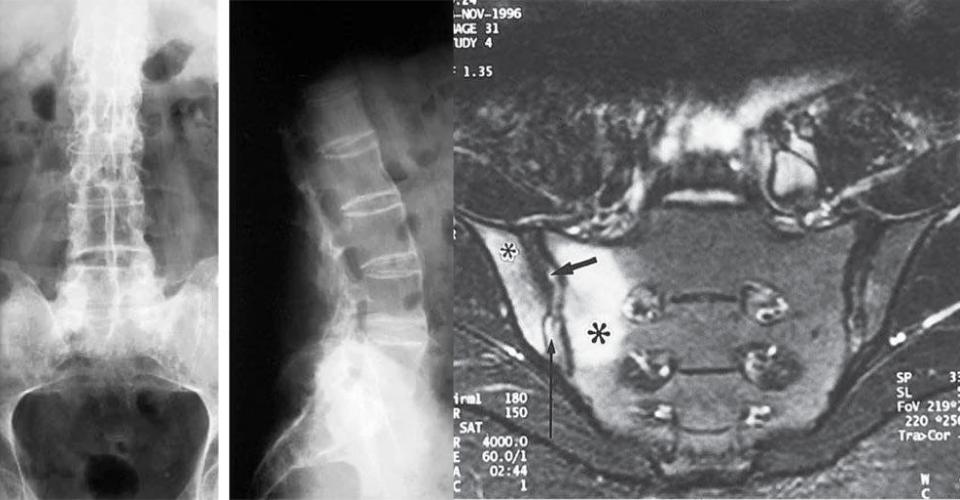

Диагностика АС